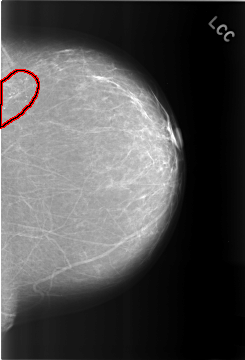

C_0317_1.LEFT_CC

FILE: C_0317_1.LEFT_CC.OVERLAY

TOTAL_ABNORMALITIES 1

ABNORMALITY 1

LESION_TYPE CALCIFICATION TYPE PLEOMORPHIC DISTRIBUTION CLUSTERED

ASSESSMENT 4

SUBTLETY 5

PATHOLOGY BENIGN

TOTAL_OUTLINES 1

BOUNDARY